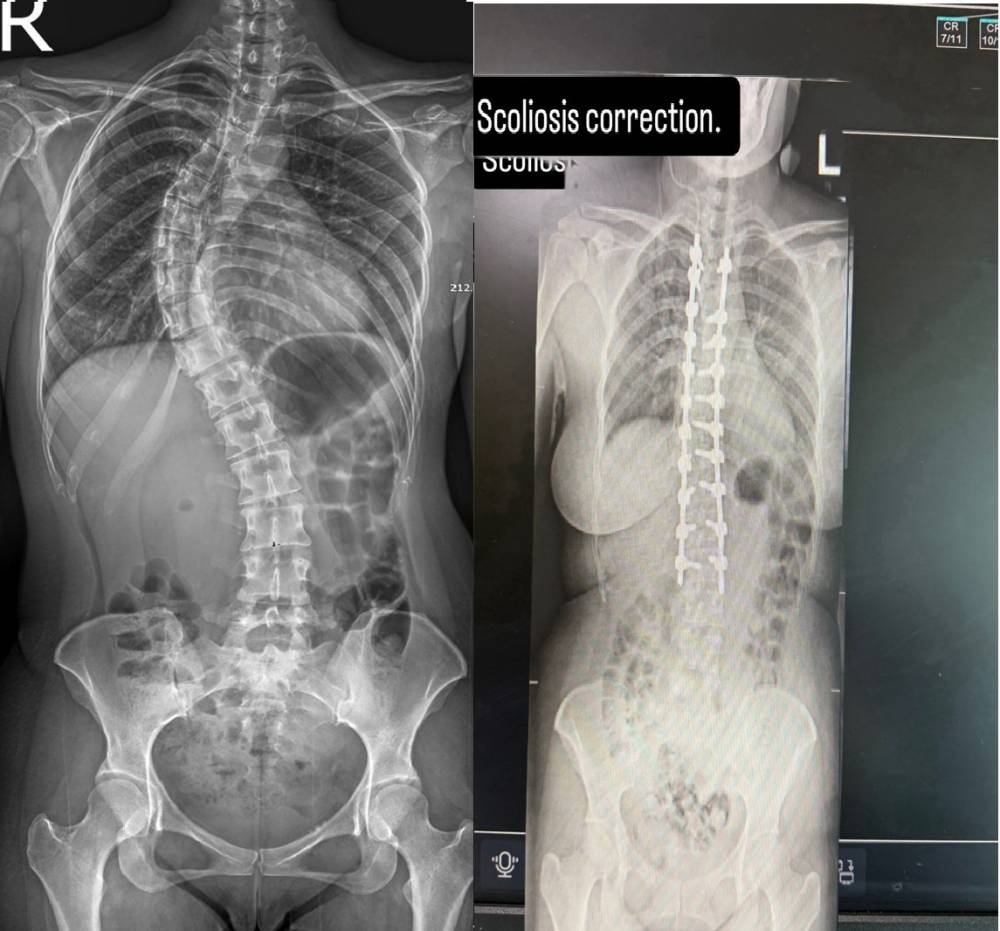

حقق مستشفى السعودي الألماني دبي إنجازاً إقليمياً بارزاً من خلال إجراء أول عملية «تاولينوبلاستي» في الشرق الأوسط، وهي تقنية مبتكرة وطفيفة التوغل تُجرى من خارج التجويف الصدري لإصلاح تشوه تقعر القفص الصدري (الصدر الغائر). أجريت العملية لطفلة مصرية تبلغ من العمر 11 عاماً تعاني...